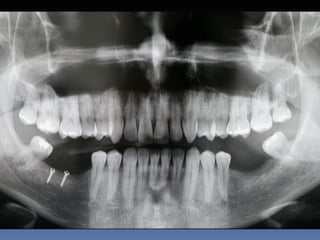

Edilson Almeida

Idade – 41 anos

Sexo – Masculino

Raça – Caucasiana

ASA – I

Data- 28-04-2012

Diagnóstico: Desdentado bilateral

Posterior da mandíbula. Regeneração

óssea vertical – zona 4.6, 4.7.

.

Plano de tratamento: Instalação de implantes endo-

ósseos ( 3.6,3.7,4.6,4.7 ) para reabilitação protética

fixa.